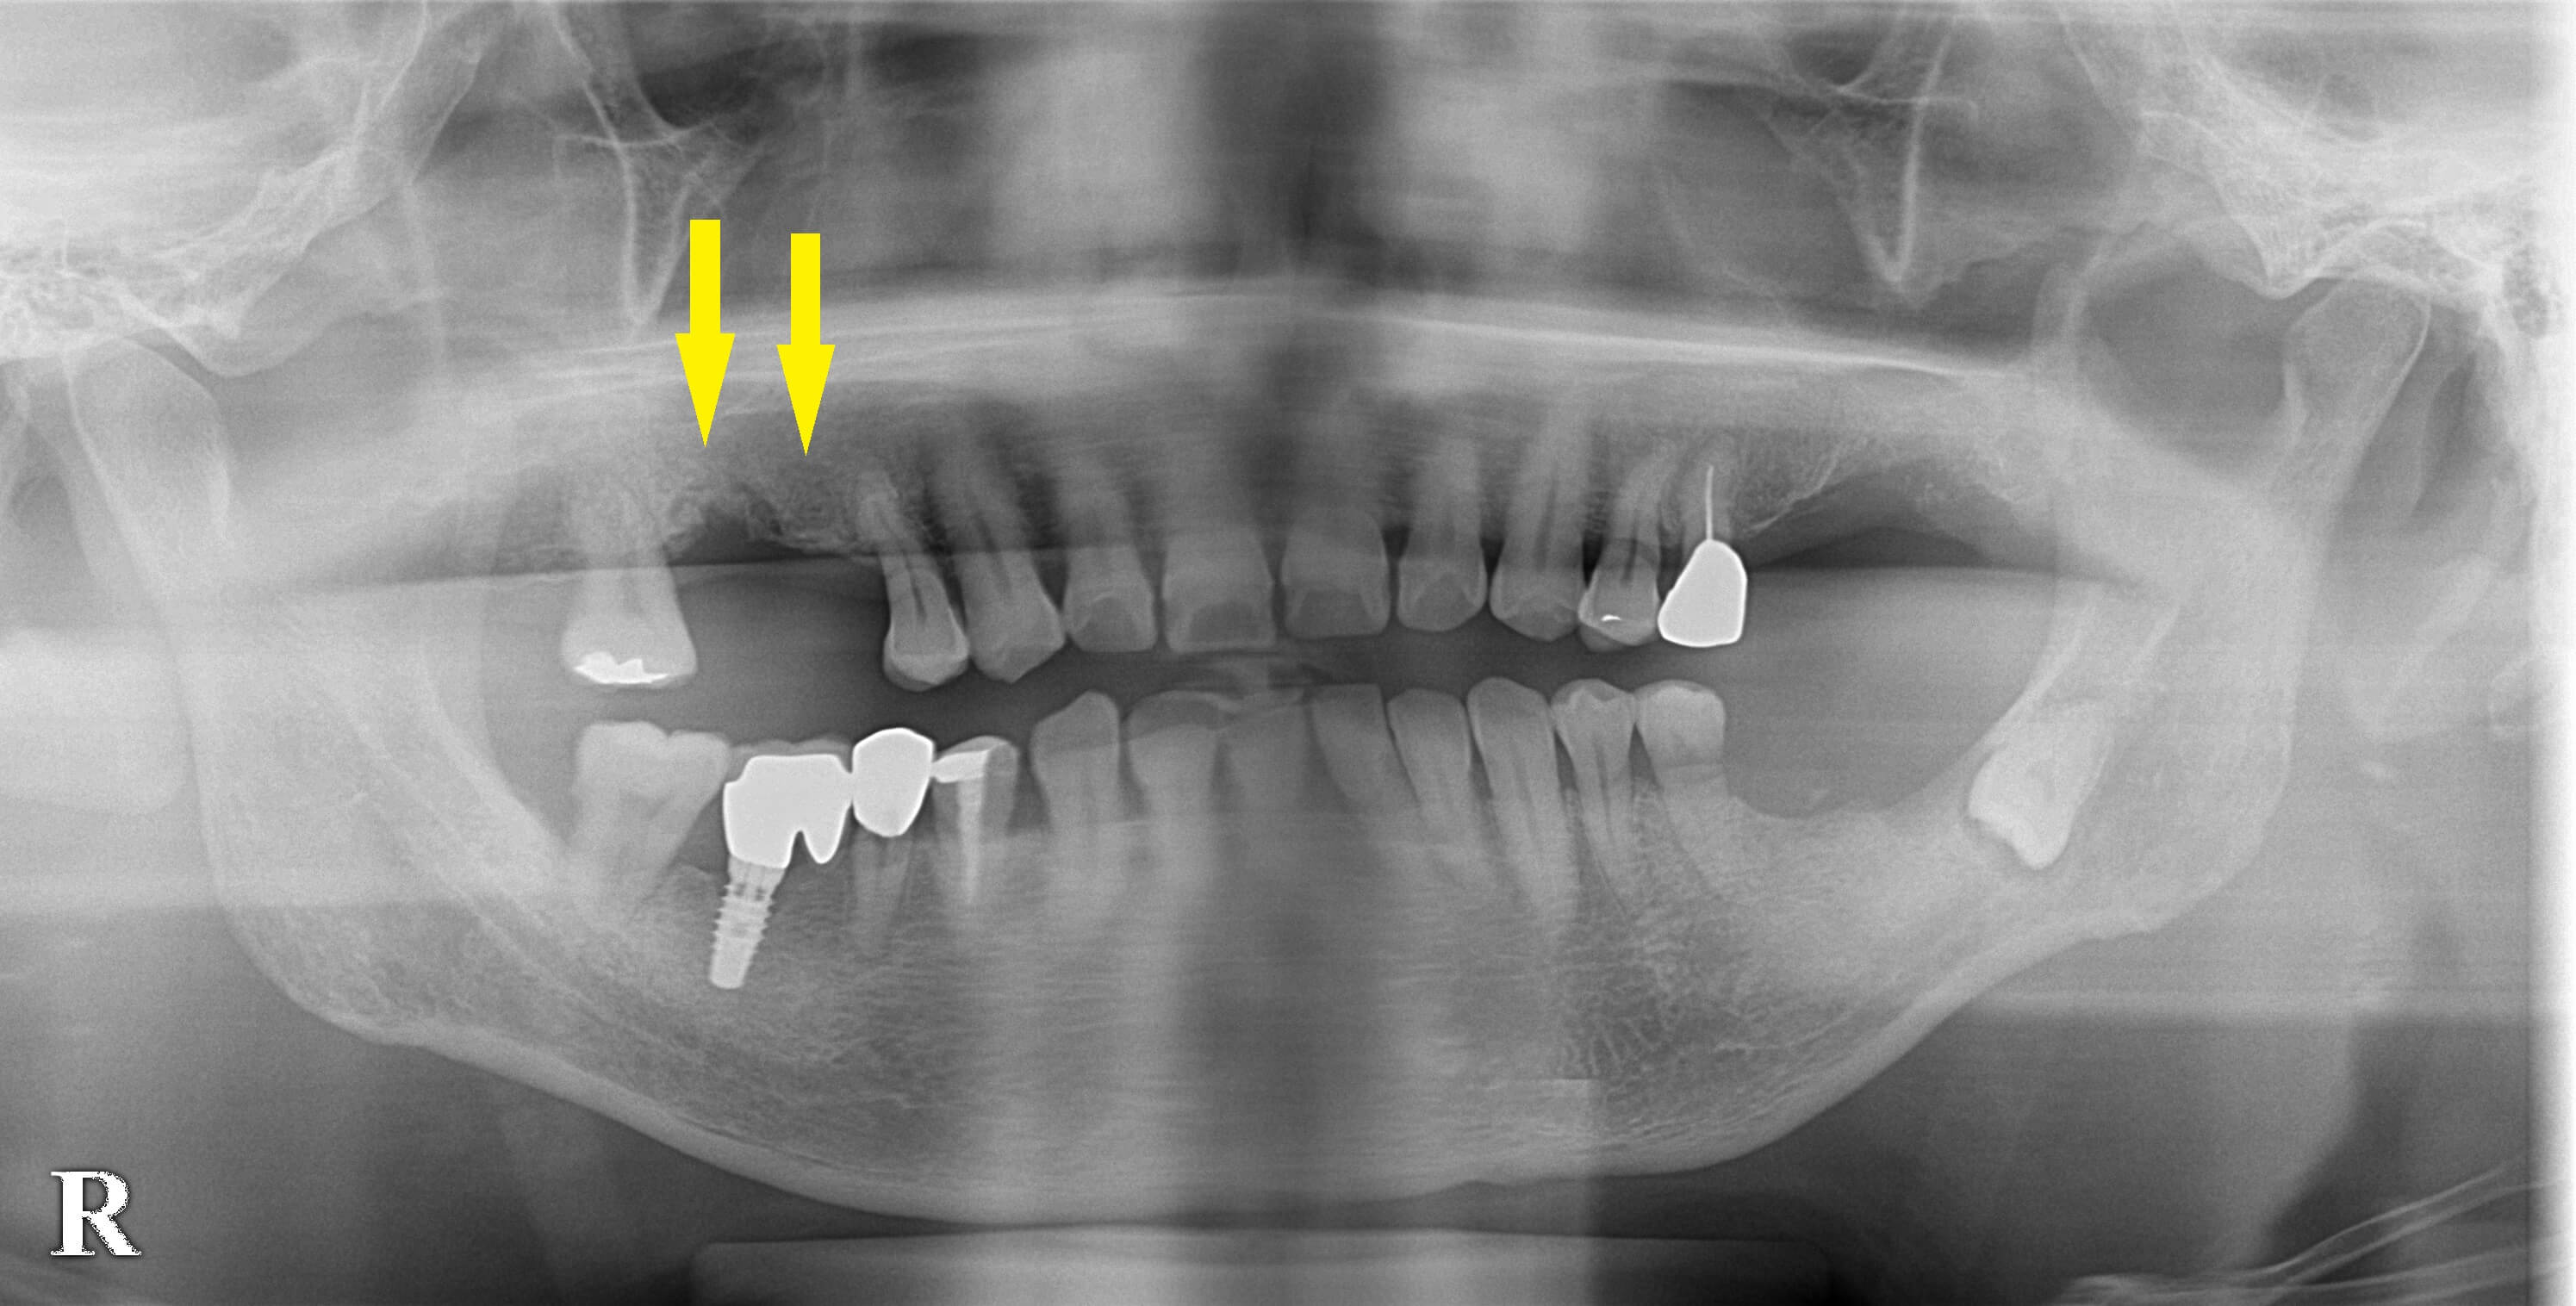

今回、右上顎臼歯が抜けてしまい、この部位のインプラント治療を希望されて来院されました。

CTを撮ってみると、前方の部位の骨量に問題はありませんが後方の骨の高さがやや不足していました(下段左の写真)。

本日、2本のインプラント埋入を行い、1本はソケットリフトを併用しました。

下段右の写真が、手術後のCTです。

インプラント上方に、骨補填材が填入されています。